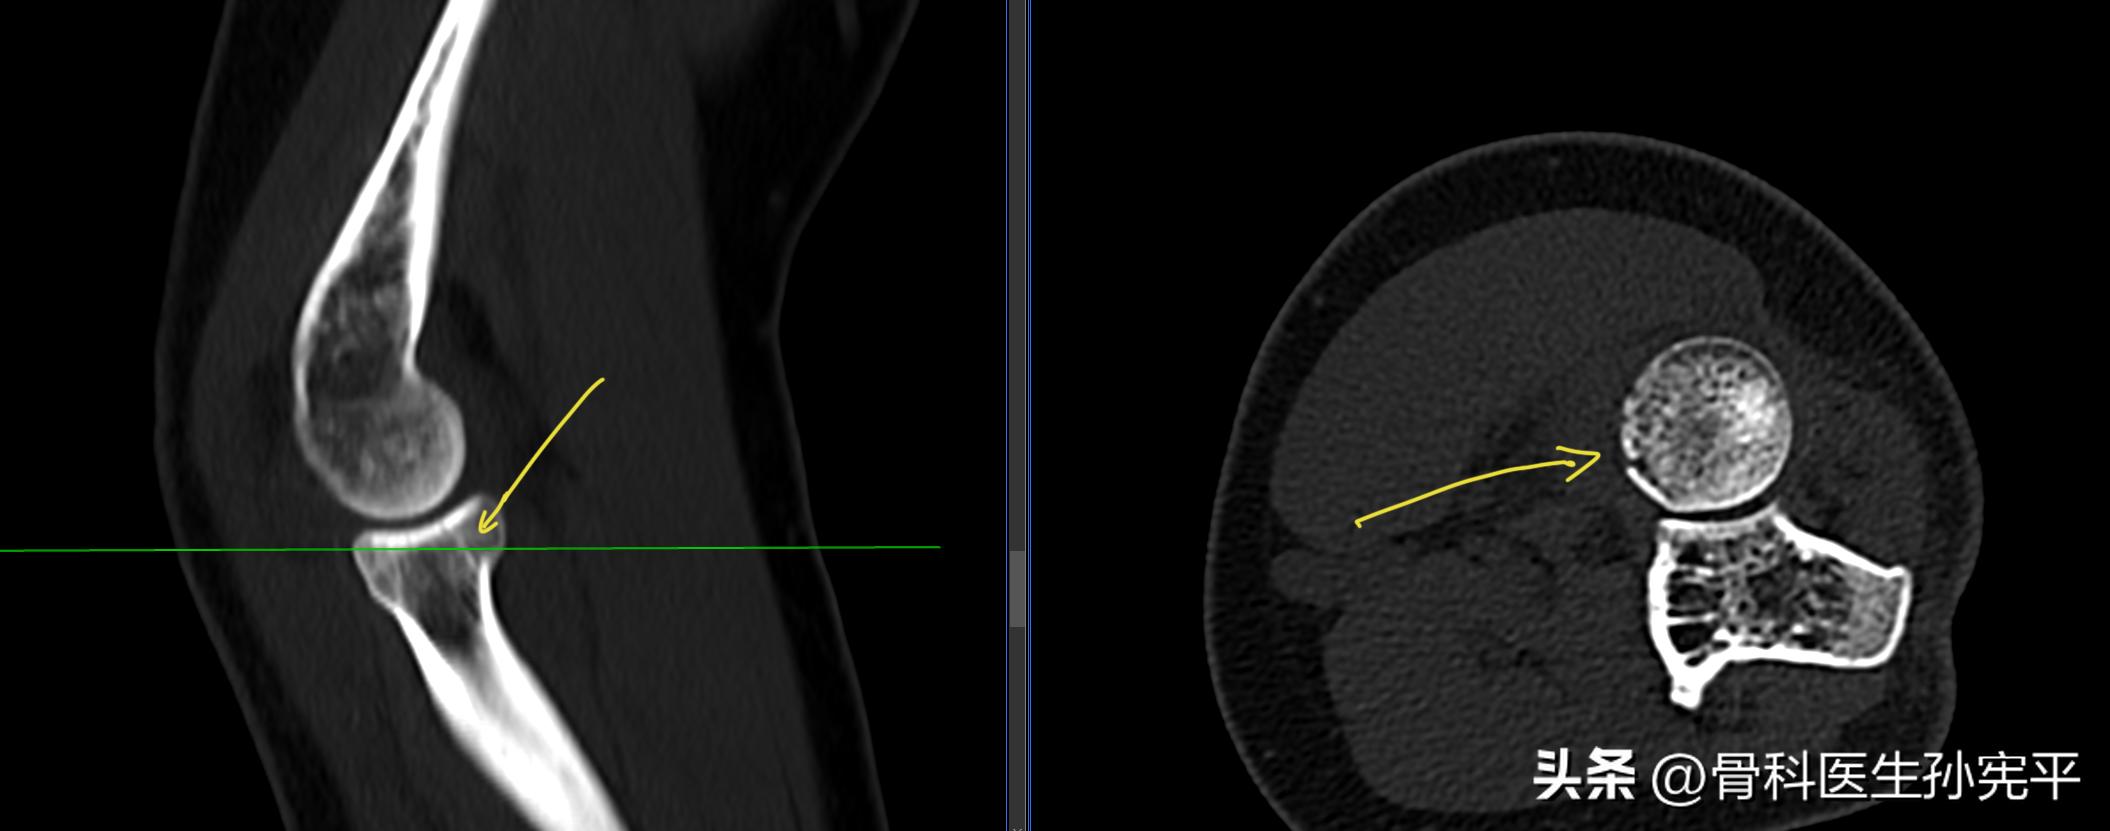

病例5:摔倒后左肘关节疼痛3小时。

肘关节“船帆征”

阅片未见明显骨折征象,但可见左肘关节前侧脂肪垫征“船帆征”改变。进一步查肘关节CT,结果如下:

左桡骨小头骨折

脂肪垫征又称作船帆征或八字征,当肘关节损伤时,关节腔内积液或出血,关节囊肿胀,在X线片上可能会出现肘前/后脂肪垫影。细微的软组织表现对肘部损伤十分重要,不应疏忽,脂肪垫征可见于肱骨髁上骨折、外侧髁骨折、桡骨小头骨折等。虽然脂肪垫征≠骨折,但骨折概率明显增大,对于有外伤史的病人可能X线片未见明显骨折征象,但对于出现船帆征或八字征的病人要定期复诊、复查,必要时行肘关节CT或核磁检查,进一步明确是否合并骨折。